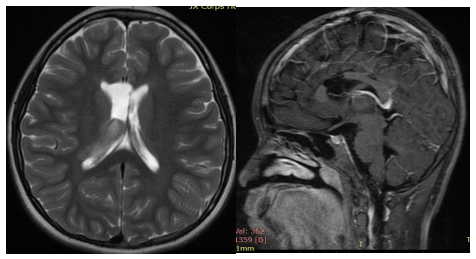

5、童童,8岁,右侧丘脑胶质瘤术后,多中心II级胶质瘤可能。复查头颅MR示:右侧丘脑胶质瘤术后改变;右侧内囊膝部及丘脑异常信号。